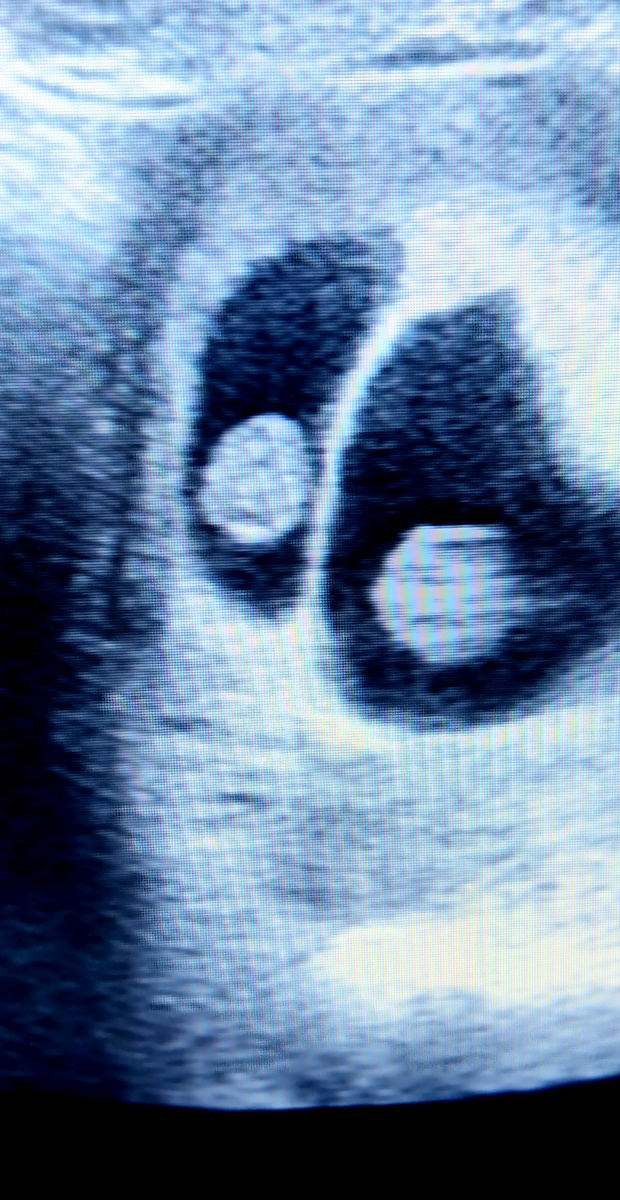

Une femme enceinte de jumeaux a-t-elle des besoins nutritionnels particuliers?